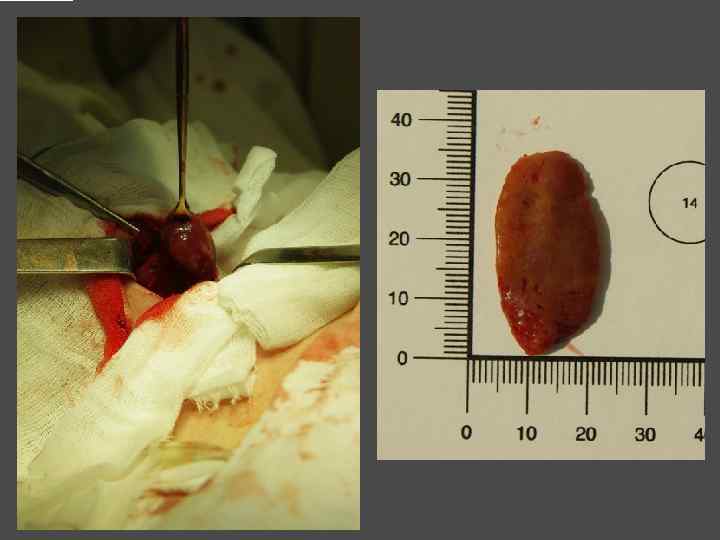

ВИДЫ ХИРУРГИЧЕКИХ ВМЕШАТЕЛЬСТВ ► Энуклеация ► Резекция щитовидной железы (доли) ► Тиреоидэктомия (гемитиреоидэктомия)

ХИРУРГИЧЕСКОЕ ЛЕЧЕНИЕ ЗОБА

ОСЛОЖНЕНИЯ ХИРУРГИЧЕСКОГО ЛЕЧЕНИЯ ►Поражение возвратного нерва, приводящее к параличу голосовой связки на стороне поражения, как следствие – изменение тембра голоса, сужение голосовой щели, затруднение дыхания. ► Кровотечение. ►Тиреотоксический криз. ► Гипопаратиреоз. ► Рецидив тиреотоксикоза. ► Формирование порочного рубца.